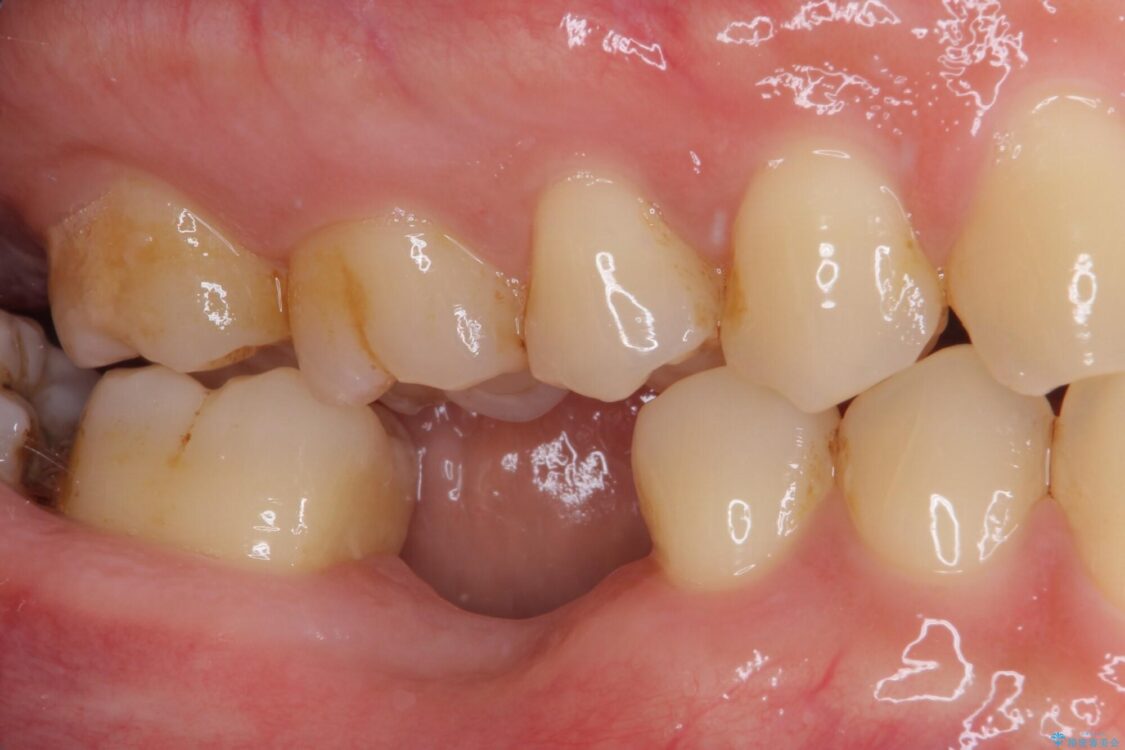

治療前

• 空いている時間を利用して通院 奥歯のインプラント治療 治療前画像